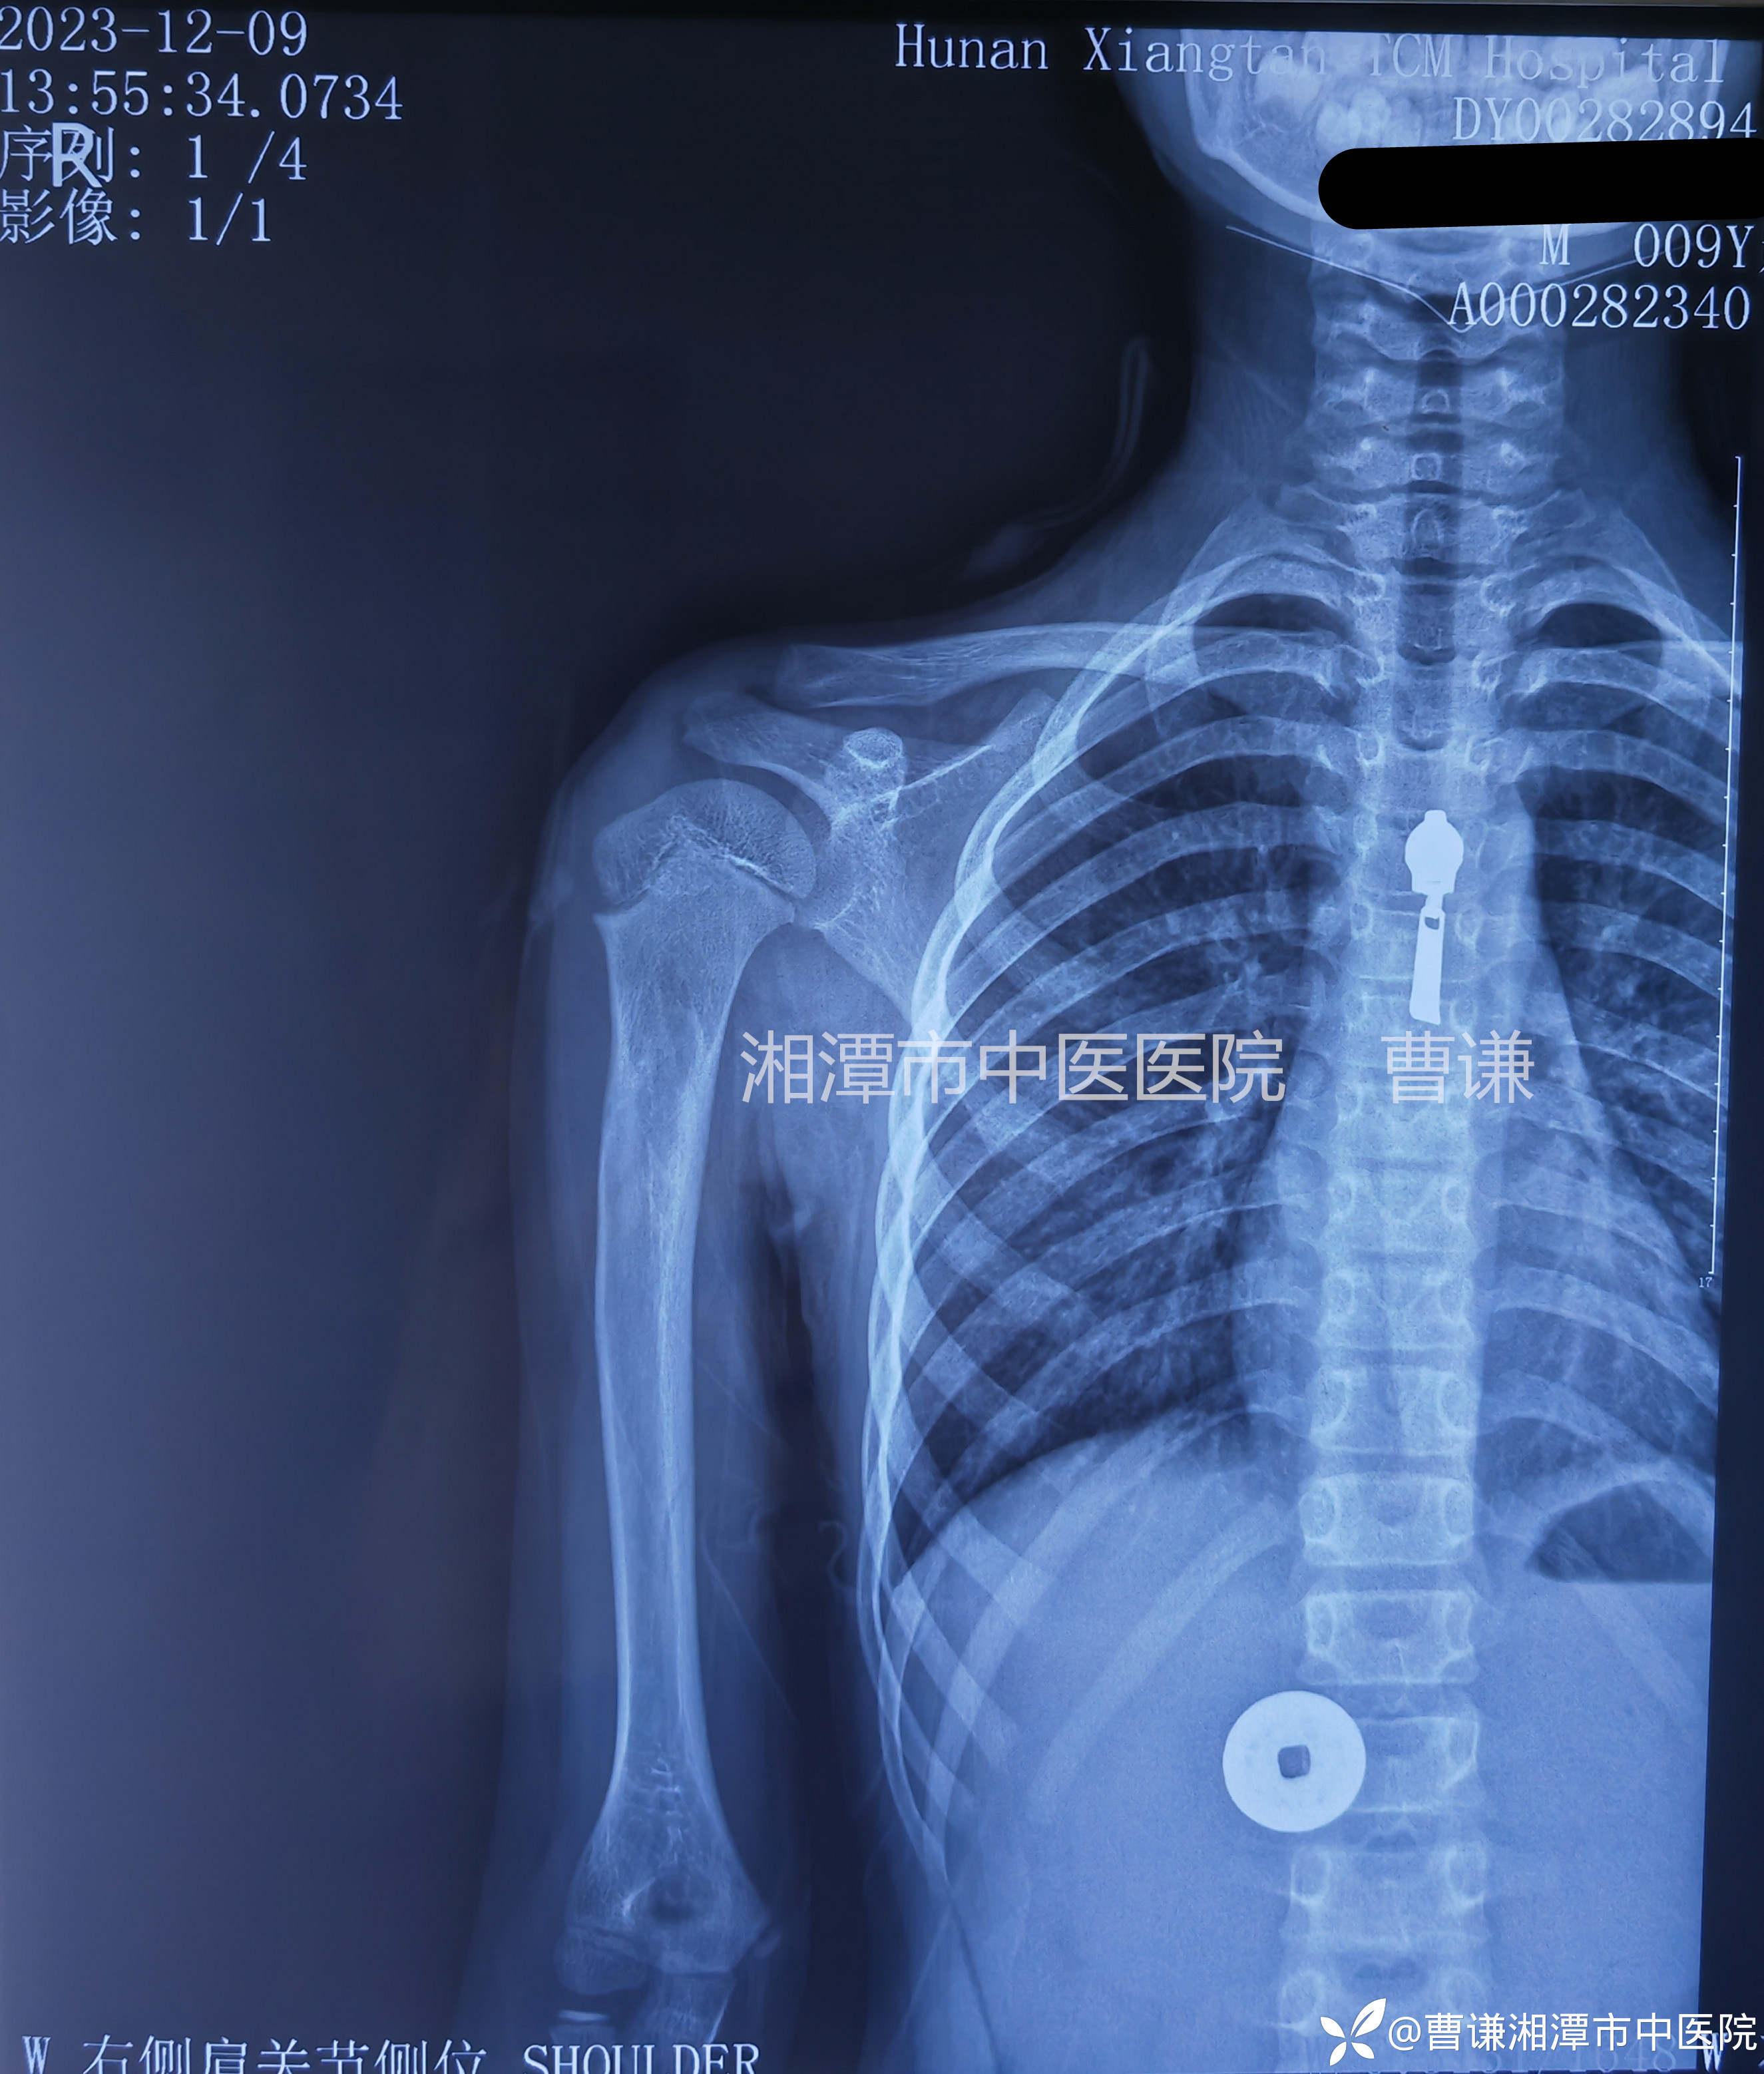

辅助检查:X线片:右肱骨近端骨折,断端错位明显。

临床诊断:右肱骨近端骨折。

患者跌倒致右肩部肿痛,活动受限,就诊于当地医院,拍片示右肱骨近端骨折,初看片子似乎骨折对位良好,其实仔细看可以发现断端重叠明显,虽然拍了两个片子,但其实都是正位,当地医院建议手术治疗,患者家属拒绝手术治疗,转来我院要求保守治疗。

讨论:儿童肱骨近端骨折相对少见,占所有儿童骨折比例的0.5%,一般儿童肱骨近端骨折预后较好,很少会导致功能受损,所以通常可以行非手术治疗。儿童有强大的塑形能力,特别是年龄小于11岁的患者重塑能力较强,不管骨折是否移位,非手术治疗都可以获得较好的结果。

由于干骺端血运丰富,错位明显的骨折会导致断端出血较多,肩部肿胀明显,影响复位,我们不必强求骨折解剖复位,只要使骨折端靠拢,维持稳定,等待骨折愈合塑形即可,避免暴力复位增加医源性损伤。

由于骨折端出血较多可能导致有瘀血填充到关节囊,形成肩关节半脱位的假象,无需特殊处理,适当进行肩关节被动活动可以加速肩关节半脱位的改善。